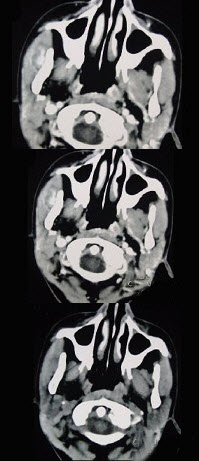

- 单项选择题16岁女性患者,右侧面颊部肿胀,CT扫描如图所示,应考虑为()。

A、右侧咬肌区血管瘤

B、右侧咬肌区脂肪瘤

C、右侧咬肌区皮样囊肿

D、右侧咬肌区淋巴管瘤

E、右侧咬肌区慢性淋巴管炎

- A